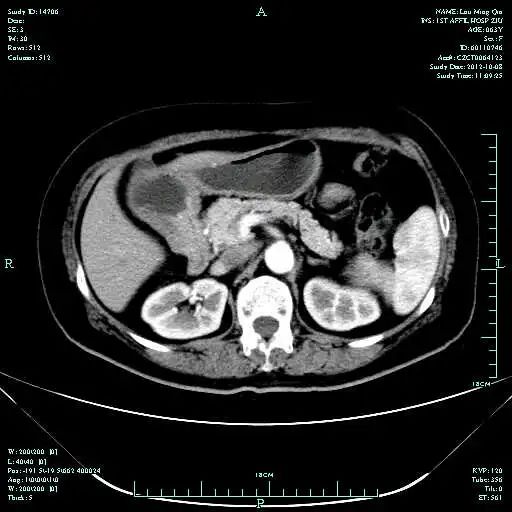

经院内MDT讨论后:2013.6.13 行“肝转移灶切除+右半结肠切除+胰十二指肠切除+Child重建”

术后病理:(胃窦部)溃疡型中低分化腺癌伴淋巴结转移性癌,侵犯十二指肠及胰腺;(肝)腺癌浸润或转移,符合胃肠道来源

TNM分期:pT4bN1M1(Ⅳ期) HER2 IHC +++